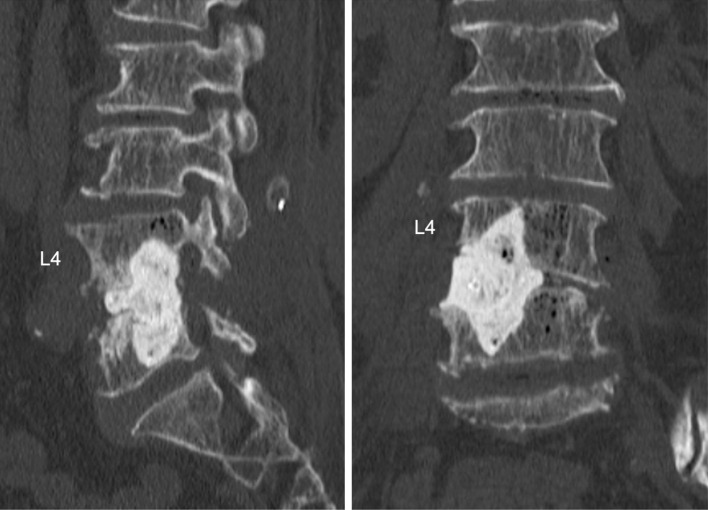

Abstract Image